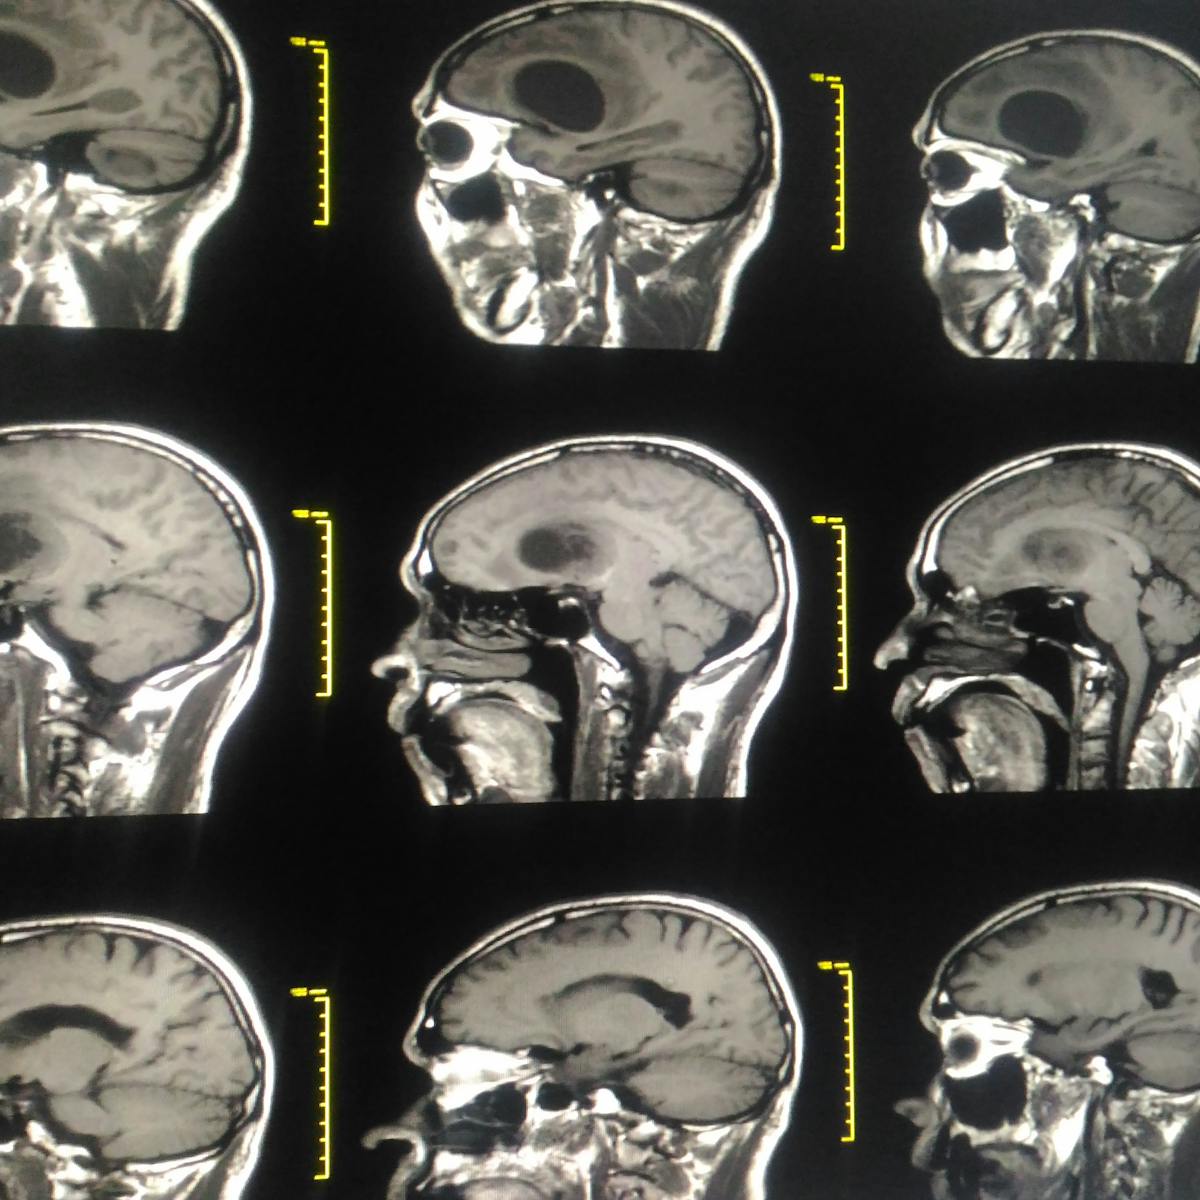

Other types of bone cancer are chondrosarcoma fibrosarcoma and hemangiosarcoma. Patients with asymptomatic skull metastases and without brain metastases were followed up with regular mr imaging. The usual treatment for bone cancer is surgery and it has a good outlook.

Primary refers to cancer that starts in the bone versus spreading metastasizing into the bone from somewhere else. However bone cancer of the skull in dogs is not unknown and there are several forms of this type of cancer. Bone cancer develops in the skeletal system and destroys tissue.